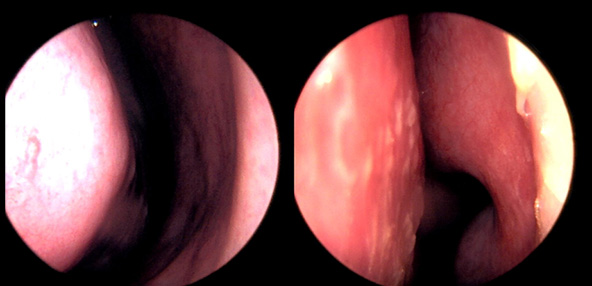

본 사진은 의료기관에서 진료를 본 환자이고, 전후 사진 인물이 동일인이며,동일조건에서 촬영이 되었습니다.